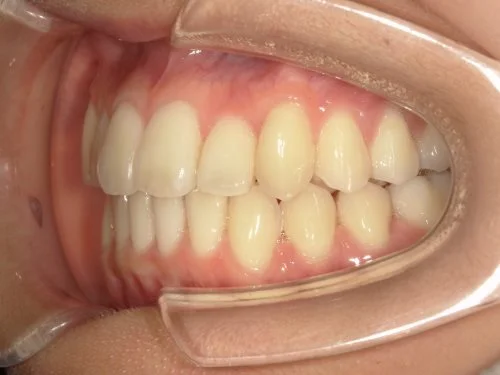

<症例3>前歯のクロスバイトでお悩み

右上の前歯2本が反対に咬合している、いわゆるクロスバイトが主訴でご来院なさいました。

主訴以外の部分には大きな叢生はなく、また患者様も装着時間をしっかり守ってくださったので約6ヶ月で改善することができました。

患者様と症状

主訴:上の前歯が出ている

性別・年齢:20代女性

問題点:上顎左側側切歯のクロスバイト、叢生

診断:前歯部の叢生を伴うアングルⅠ級の不正咬合

主なリスク:矯正中一時的に咬合しにくくなる、歯肉退縮

症状:叢生(そうせい) 上顎前突(じょうがくぜんとつ)

治療内容

治療期間:6ヶ月

治療費用:495,000円(税込)

プラン:14枚コース/ライトプラン

抜歯:親知らずのみ抜歯

再診治療費:無し

追加治療費:無し

保定装置費:無し

治療前後の写真

・2本の前歯が前突しておりましたが、矯正で自然な歯並びになりました。

・前歯の1本が下の歯の裏側に噛み合うクロスバイトになっていましたが、矯正で改善されました。